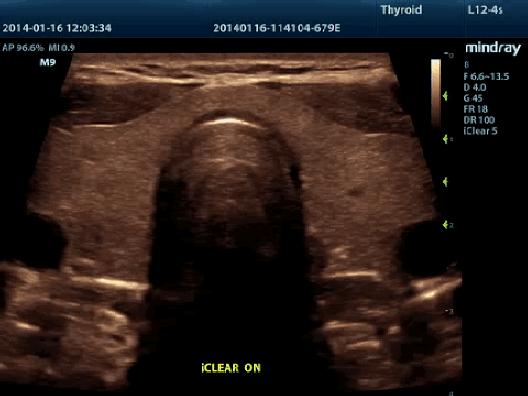

iClear™

Позволяет улучшить качество изображения, основываясь на автоматическом распознавании структур.

- Более четкие края и контуры

- Плавное и однородное отображение тканей

- Снижение зернистости в «областях без эхосигнала»